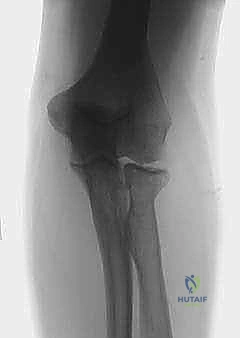

- Sauvรฉ-Kapandji Procedure: A Masterclass in Distal Radioulnar Joint Reconstruction